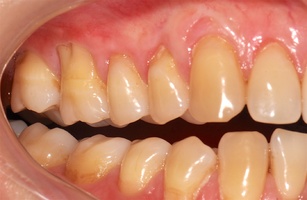

В марте 2017 года в клинику обратилась пациентка Ч., 28 лет (табл. 1) без вредных привычек, с положительным социальным статусом, астенического телосложения. С жалобами на тотальное обнажение корней зубов с повышением чувствительности от термических раздражителей, эстетические дефекты, абразии твердых тканей зубов.

Исходный объем мягкотканного комплекса атрофичен, тонкий биотип десны. Мелкое преддверие полости рта на нижней челюсти в переднем отделе, от 44-го до 34-го зубов высокое прикрепление слизисто-мышечных тяжей.

Форма зубной дуги — эллипсовидная, с незначительным сужением в области премоляров на верхней челюсти; во фронтальных участках верхней и нижней челюстей окклюзия в протруссии. Зубы крупные, вытянутые по форме. Межальвеолярный контакт в норме, прикус ортогнатический. Гигиенические индексы: IG–1,2(HYG),PI—6,GI—0,PBI—0.

В области от 1.6 до 2.6 и от 3.6 до 4.6 все зубы имеют некариозные поражения разной степени, такие как эрозии эмали и клиновидные дефекты, вовлекающие в процесс ткани эмали и дентина. Подвижности зубов не выявлено (рис. 1а-е) [9].